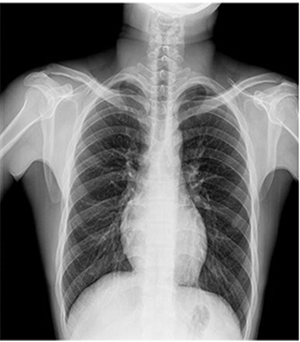

PLD6500系列是普利德研发的医用数字X线摄影机,采用双立柱结构,可供各级医院放射科对头部、胸部、腹部、腰椎、四肢等部位进行立位、卧位、正位、侧位的数字摄影检查。